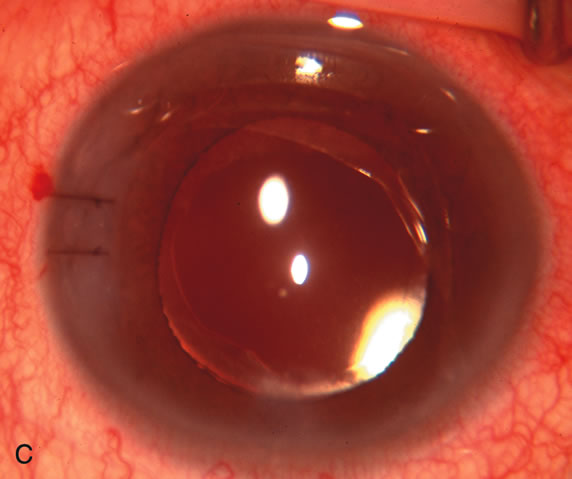

Fig. 3. Partial bleb failure following clear corneal phacoemulsification with foldable IOL. A. Preoperative bleb appearance prior to temporal lens extraction. Preoperative IOP was 12 mm Hg on no antiglaucoma medications. Time from 5-FU trabeculectomy surgery to lens extraction was one year. B. Bleb appearance 2 months after clear corneal cataract surgery with topical anesthesia. Following lens extraction, increased vascularity was noted along with decreased size of the filtering bleb. IOP increased to 20 mm Hg as early as 2 weeks after surgery, necessitating topical antiglaucoma therapy. C. High magnification view of bleb before lens extraction demonstrates diffuse pale bleb. D. High magnification view of bleb 2 months after surgery. There are vessels surrounding the nasal side of the bleb and the overall bleb size is smaller.